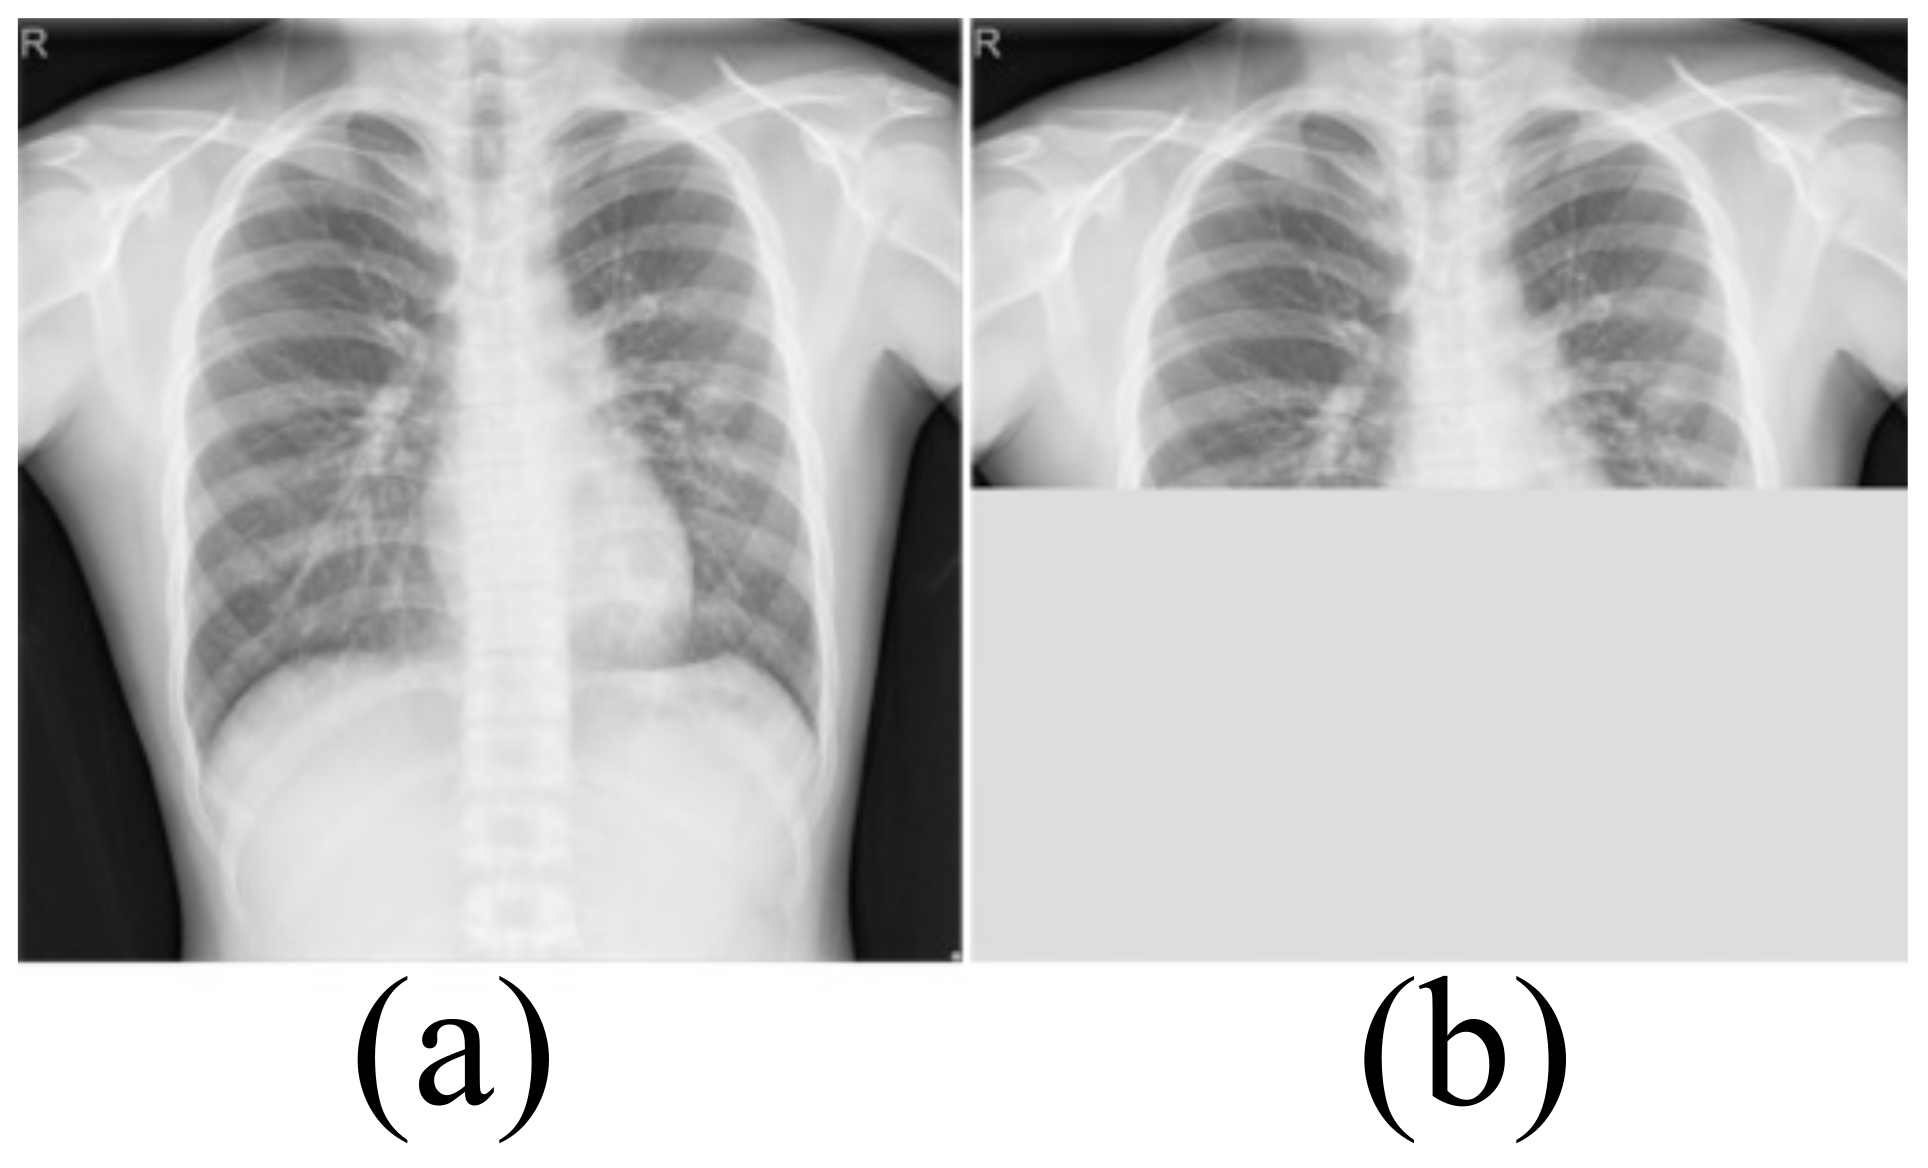

Medical image datasets contain fewer samples and often require data enhancement to increase the number and complexity of training samples. Data enhancement can make the training samples contain the type of test samples as much as possible, and improve the generalization ability of the network. We first perform a horizontal flip of the training sample and a rotation transformation between −20 degrees and 20 degrees with an interval of 5 degrees. These basic transformations can simulate the different postures of the person when doing the examination. The Montgomery dataset and Shenzhen Hospital (SH) dataset only include CXRs of healthy people and patients with moderate pneumonia. In order to simulate the presence of a large number of opacities in the lungs, we use block masking. We think of a large number of opacities in the lungs as missing data. As shown in Figure 2, the block masking simulates the opacities, increasing the complexity and diversity of the samples. If the width of the block masking is equal to the width of the image, the height of the block masking is half or one-third of the image’s height. If the height of the block masking is equal to the height of the image, the width of the block masking is half or one-third of the image’s width.

Figure 2.

The block masking. (a) Original image (b) With block masking.